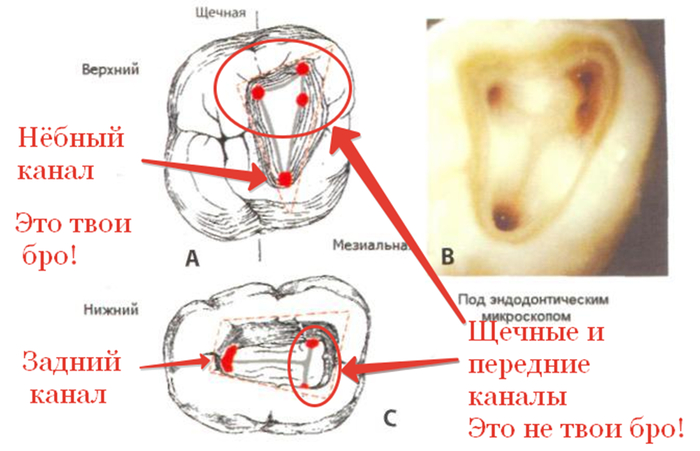

-Анатомия некоторых корневых каналов не всегда позволяет их распломбировать их так. Чтобы не ослабить потом зуб. Например, небный канал у верхних 6 и 7 зубов и задний канал у нижних, как правило, прямые, широкие, с толстыми стенками. Их легко найти, легко расширить до нужного размера, чуть ли не до самой верхушки. Если говорить про щечные и передние каналы, то они, как правило, узкие, кривые, с тонкими стенками, их устья находятся где-то в заднице. Также их корни имеют различные инвагинации и поднутрения, отчего даже просто их пролечить или запломбировать становиться проблемой, не то, что засунуть туда штифт и дать на него нагрузку.